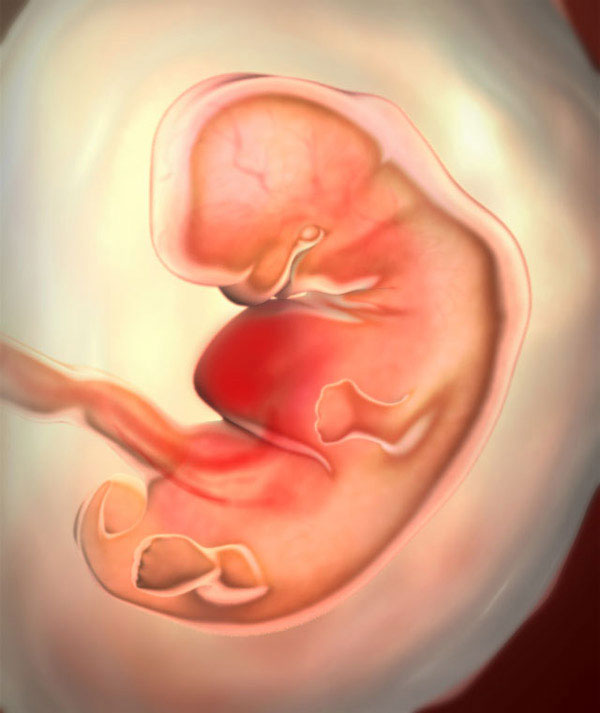

What does the future baby look like?

The largest parts of the body are the head and torso. The arms and legs are tiny processes with tubercles-fingers. The size of the fetus (more precisely, the embryo) in the 6th obstetric week reaches 4 mm, weight - up to 2 g. And here is how it develops:

• limbs gradually lengthen, knee and elbow bends are outlined;

• fingers grow a little;

• cartilaginous structures develop, that is, future bones;

• the formation of the brain begins, the bone marrow is in its infancy;

• the external genitalia are hardly outlined;

• the inner ear begins to develop;

• thymus (thymus gland) is formed, the most important organ of immunity;

• lungs, heart, liver, stomach and pancreas continue to develop;

• the neural tube becomes the embryonic nervous system;

• muscle tissue is still developing rapidly.

The tiny heart regularly counts about 140 beats per minute. Is it a lot or a little? There is such a law in nature - the smaller the heart of a living creature, the faster it beats. Therefore, such a “pulse” in the embryo is in the order of things. So far, only a specialist can determine the heartbeat during an ultrasound.

By the way, the baby has a tiny tail. This is like a reminder that we are all children of Nature (after all, many living beings have tails on Earth). A little later, the tail will be pulled in and become the tip of the spine.

And here is a new miracle - the placenta is developing, the umbilical cord is forming. The baby is no longer pressed close to the wall of the fetal egg. He swims freely in the amniotic fluid and makes his first movements. But mother will not be able to feel it very soon. But she feels a lot more.